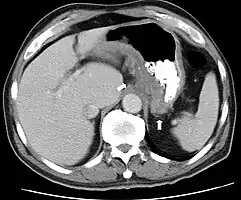

Endoscopic image of colon cancer identified in the sigmoid colon on screening colonoscopy for Crohn's disease

Some studies suggest there is a role for chemoprotection in the prevention of colorectal cancer in Crohn's involving the colon; two agents have been suggested, folate and mesalamine preparations.[59] Also, immunomodulators and biologic agents used to treat this disease may promote developing extra-intestinal cancers.[60]